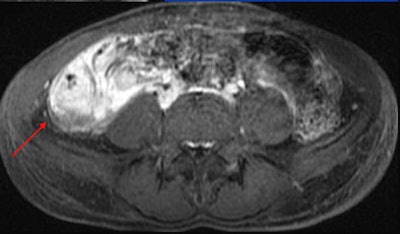

MRI results were then compared to colonoscopy and pathology reports to determine the presence or absence of disease in evaluable bowel segments. Individual imaging parameters (including wall thickening, enhancement, T2 signal, mesenteric vascular prominence, and adenopathy) were also separately analyzed to determine their independent predictive value, the authors wrote.

The study team acquired steady-state free-precession (SSFP) images of the abdomen and pelvis (TR= 4 ms, TE = 2 ms, slice thickness 8 mm for coronal images and 8-mm for axial images). Axial and coronal fat-suppressed half-fourier single-shot fast-spin echo (SSFSE) and axial spoiled-gradient images were also obtained through the abdomen, followed by T1-weighted fat-suppressed spoiled-gradient echo (LAVA/VIBE) images, before the injection of 1 mmol/kg of gadopentate dimeglumine contrast (Bayer Healthcare) followed by a saline flush and postcontrast imaging.

A single experienced abdominal radiologist, blinded to the final results, interpreted all of the MRE images, rating wall thickness, abnormal enhancement, abnormal T2 signal, and mesenteric vascular prominence on a scale of 1-4. All endoscopy reports were reviewed for mention of inflammatory changes in specific bowel segments, and pathology reports were reviewed for the presence of inflammatory disease, the study team reported.

Interestingly, the results were in line with smaller studies that used antiperistaltic agents, they wrote. As in those studies, MRE showed its real strength in a couple of features of active Crohn's disease. "Analysis of individual MR parameters demonstrates that wall thickening and abnormal enhancement are the most sensitive indicators of Crohn's disease on MRE while abnormal T2 signal, mesenteric vascular engorgement, and adenopathy were insensitive but specific," he wrote.